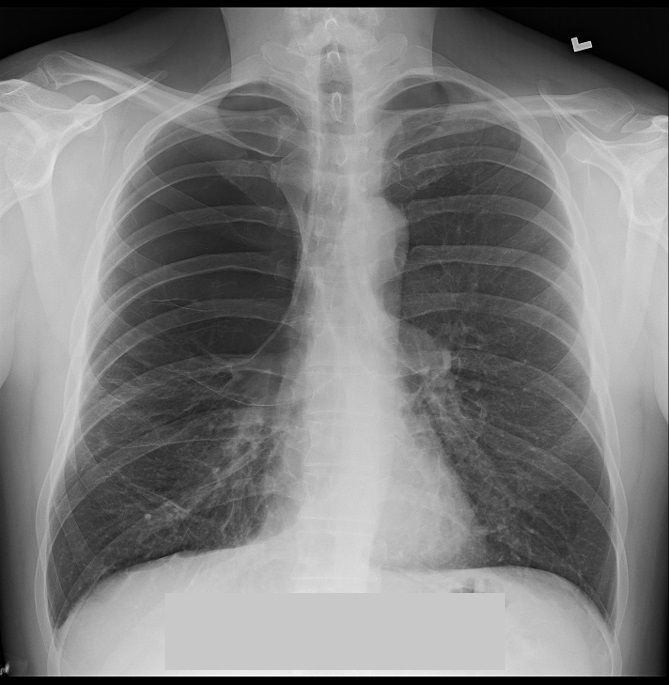

Findings on Chest X-Ray

There is a thin-walled lucency predominantly in the apical regions.